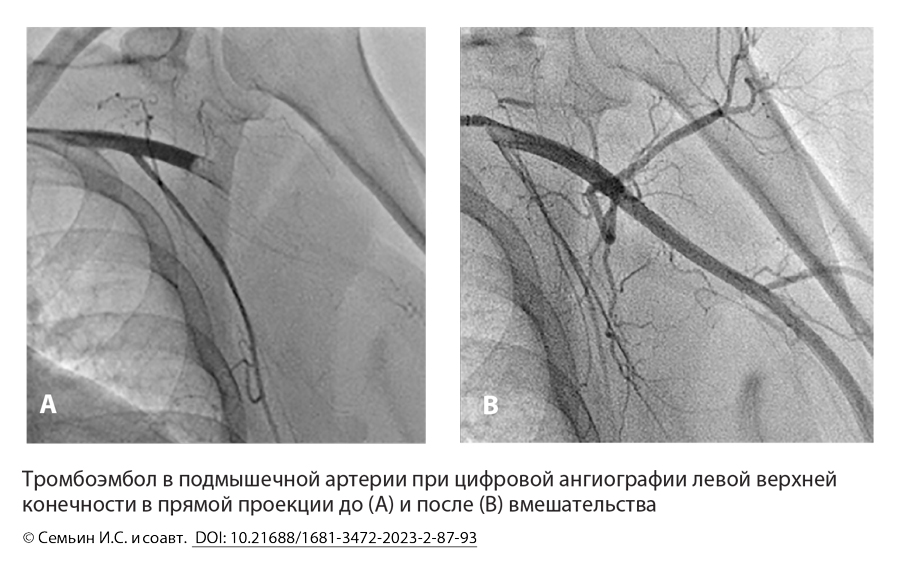

Стентовая тромбэктомия при острой ишемии верхней конечности на фоне тромбоза или тромбоэмболии: серия клинических случаев

Цель. Оценить эффективность эндоваскулярной стентовой тромбэктомии при острой ишемии верхней конечности, обусловленной тромбозами или тромбоэмболиями магистральных артерий верхней конечности.

Результаты. Первичный успех методики (полная реваскуляризация по данным ангиографии) составил 83,3 % (15 из 18 наблюдений). Изолированно метод использовали в 15 наблюдениях, в 2 случаях имплантировали саморасширяющиеся стенты, одному пациенту провели селективную тромболитическую терапию. В 3 наблюдениях явления острой ишемии не купировали, в течение госпитализации ампутаций верхней конечности не выполняли, конверсий на открытое вмешательство также не проводили. Умерли в течение госпитализации двое пациентов: в первом случае развился острый инфаркт миокарда, во втором — полиорганная недостаточность в послеоперационном периоде.

Заключение. Рассматриваемая техника эндоваскулярной тромбэктомии в комбинации с другими эндоваскулярными методами имеет высокую эффективность и такие преимущества, как малая травматичность, отсутствие необходимости в общей анестезии, точный интра- и послеоперационный контроль проходимости, своевременное выявление эмболов с возможностью их удаления из артерий, сопоставимых в диаметре с доставляющей системой стента (до 1,8 мм).